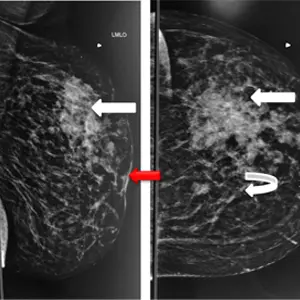

A & B) Left breast MLO and CC views showing irregular medium to high density mass in upper and outer quadrant of left breast ( straight white arrows) with associated interstitial thickening ( curved white arrow), ductal dilatation, skin thickening and retraction of the nipple (red arrow).